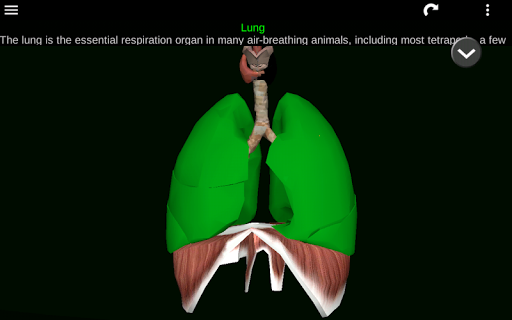

* Respiratory system, which includes the trachea, bronchi, lungs and an animation of this system.

* Descriptions of each organ.